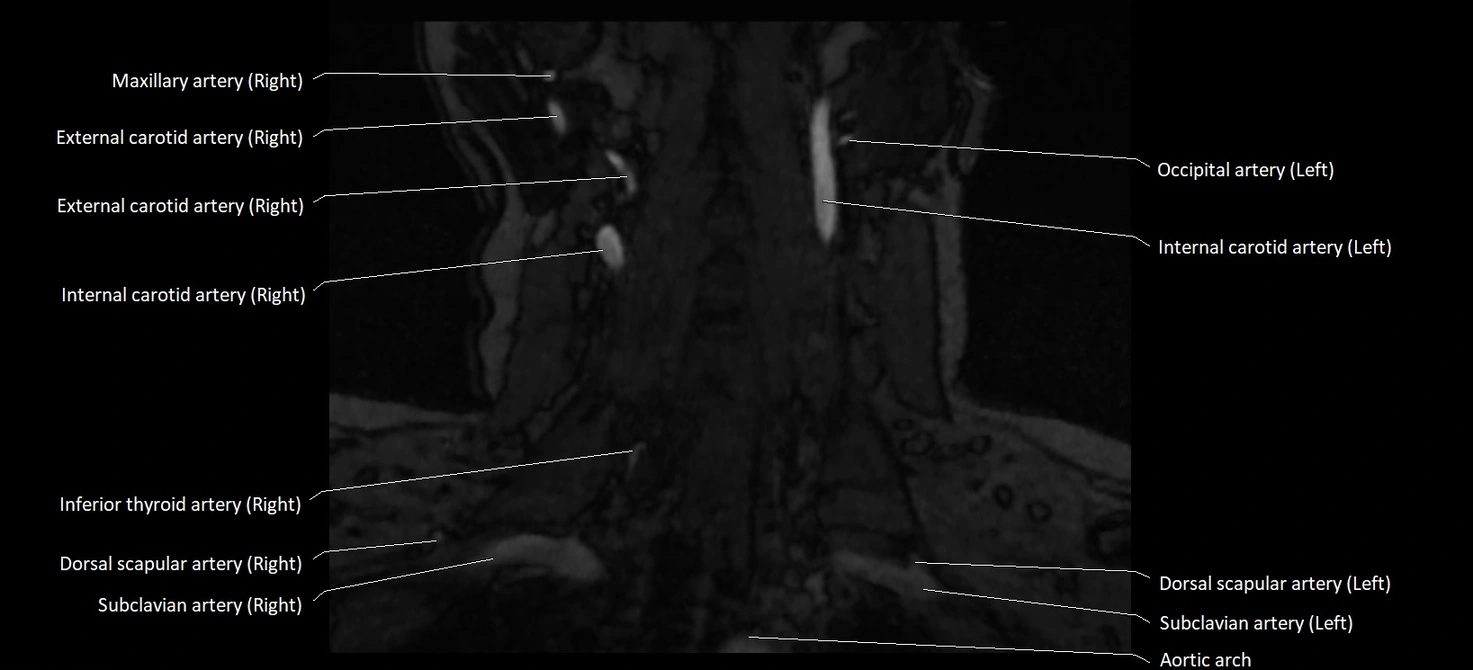

MRI images

image